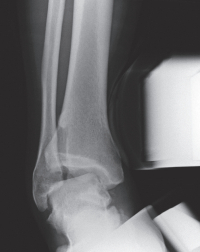

20歳の男性。右足関節の外側部痛を主訴に来院した。昨日、サッカーの練習中に右足関節を捻り受傷した。右足関節の外果周囲に皮下出血を伴う腫脹を認める。右足関節のエックス線写真と受傷肢位を強制したストレスエックス線写真を別に示す。

右足関節の状態として適切なのはどれか。

e. 不安定性